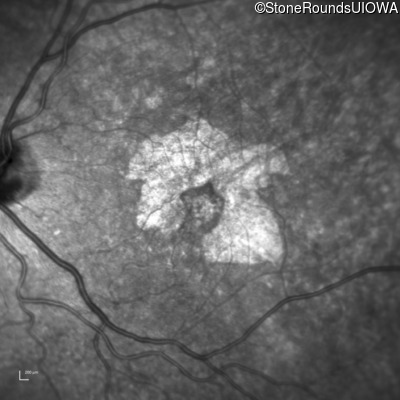

Infrared Fundus Photograph - Right - 20/32 +2

Exemplar